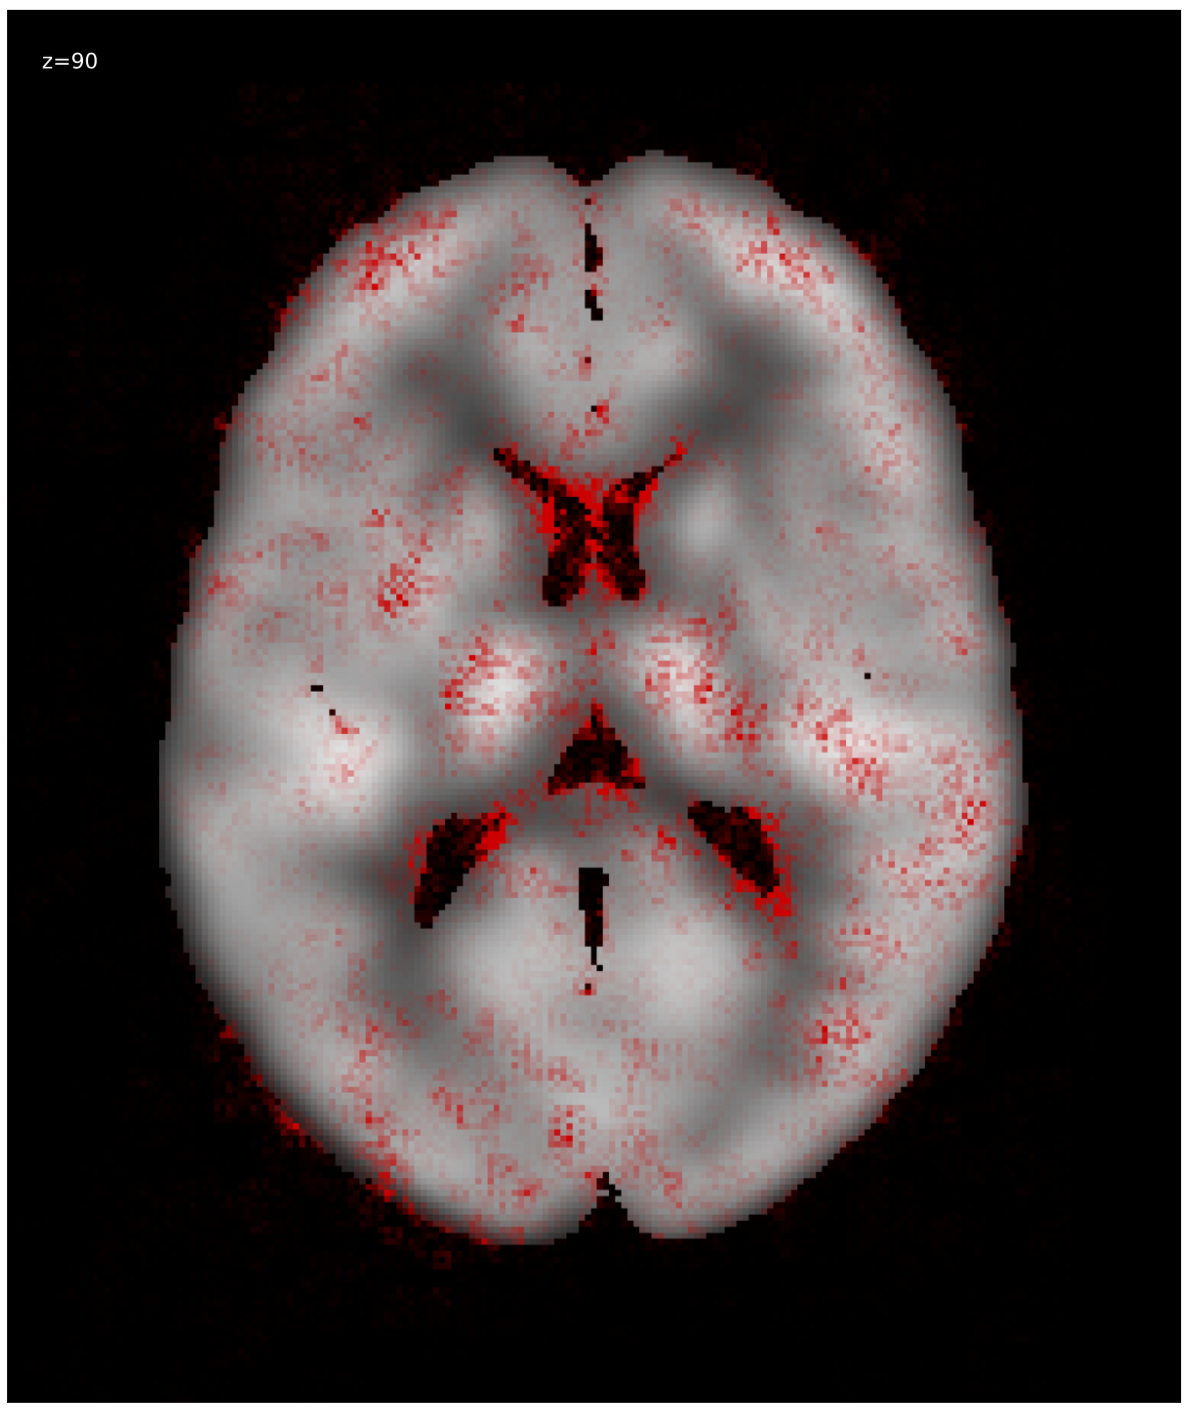

3.1 Visualization

We generated relevance heatmaps for all visualizations methods, averaged over AD PET images in the test dataset. Figure 2 presents the visual comparison of these five methods. The red areas/dots indicate that regions were important for the decision making of the 3D-CNN model. From the result, we can see that all the visualization focuses mostly on similar brain regions. There are some differences, such as the heatmaps generated for the gradient-based methods are distributed. The heatmaps highlight the areas that the CNN network is most susceptible. For the LRP method, the heatmap shows the average relevance of each voxel for contributing to the AD diagnosis score. The heatmaps generated by the occlusion based methods are more focused on the specific regions and cannot administer with large areas of distributed relevance. The reason behind the issue is the occlusion path was not able to cover those areas (for example, the cortex) completely. Brain area occlusion presents very high relevance for the temporal lobe. Since in this method, only one area is covered at a time, that can cause such high importance for one region and minimal relevance for other regions.